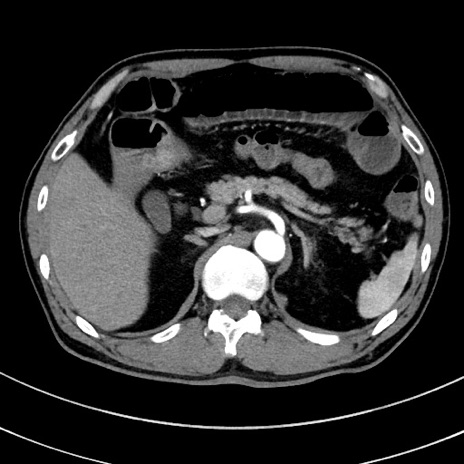

症例8(横断像)

【症例】 60歳代男性

【主訴】 黒色吐物

【現病歴】 4日前から嘔気自覚、2日前の朝食後にも嘔気あり、自分で手で嘔吐反射起こし嘔吐したところ血が混ざっていたため受診。

【既往歴】 5年前汎発性腹膜炎を伴う急性虫垂炎で手術、高血圧、前立腺肥大症、高脂血症

【身体所見】 腹部正中に手術癩痕あり 腹部平坦・軟圧痛なし膨満感あり

【データ】WBC 8400、CRP 4.54